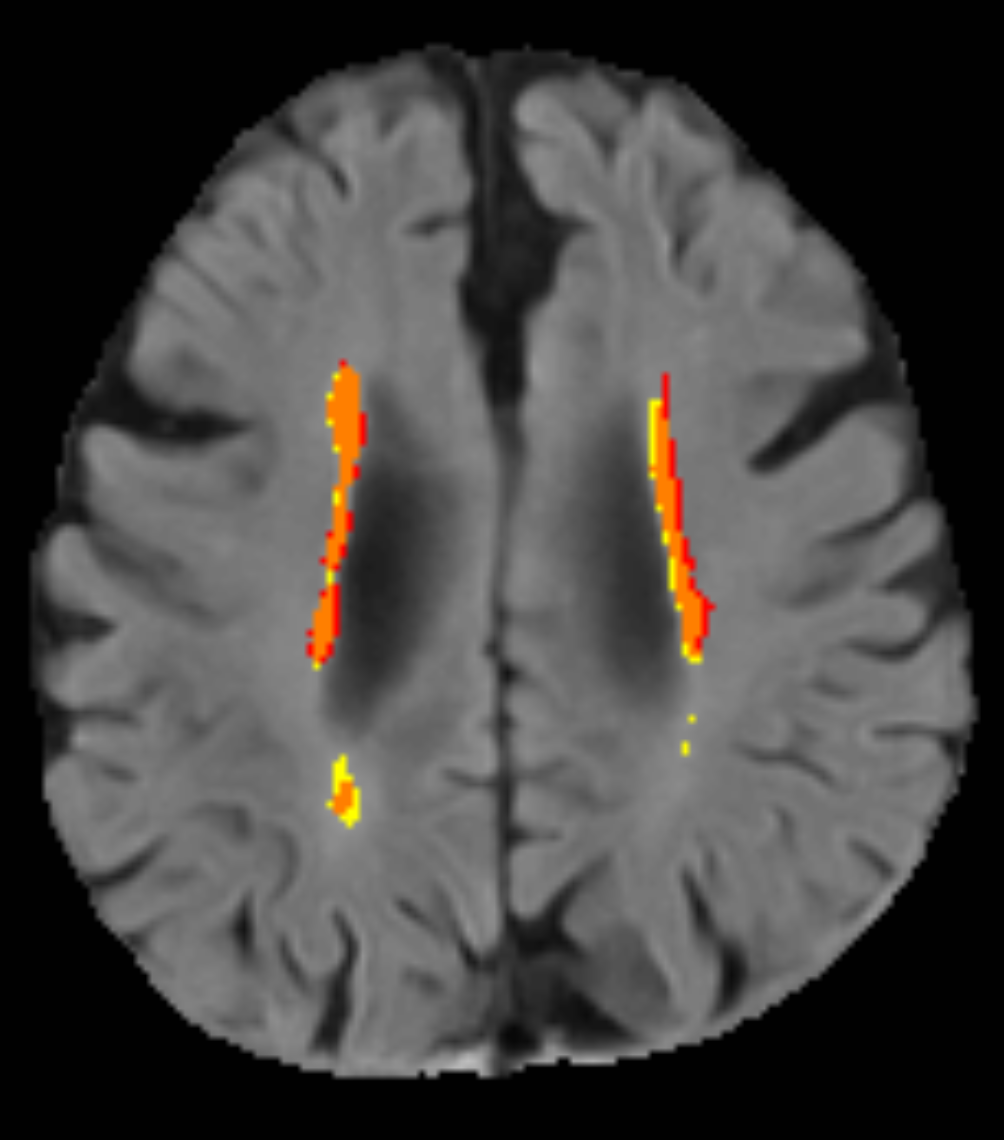

Refer to caption

(a)

(b)

Figure 5: (a) An LBC1936 FLAIR scan where it is clear that the ground truth (red) includes very small puncate areas of hyperintensity, often no larger than a single voxel, while the prediction (yellow) is more conservative; (b) An LBC1921 FLAIR scan where the ground truth does not include small disconnected WMH, but rather smoothly segmented areas of hyperintensity.

The qualitative analysis of the WMH segmentation highlighted that while the ground truth annotation policy and quality is highly variable between datasets for WMH, the model predicts in a consistent manner across datasets. This opens up another use case for our model. It allows us to use the model to gain some insight into the specific ways in which the ground truth annotation policy varies between datasets (assuming similar patient populations). This could be useful for identifying appropriate datasets to train future models, if the researcher has a preference on annotation policy type (e.g.,  conservative or not). Figure 4(b) shows that lesion-level false negatives are more common in the LBC1936 dataset than in the LBC1921 dataset, while the opposite can be said of false positives. Given the consistent way in which the model predicts, we can assume that the ground truth annotation policy for LBC1921 is more conservative than for LBC1936. Observing Figure 5 we can indeed see that this is the case.